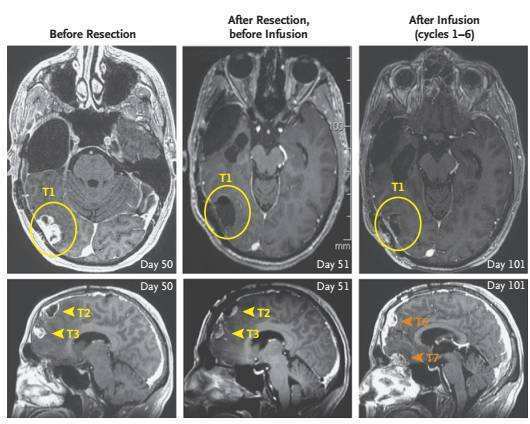

传统治疗效果不理想,于是走投无路的Richard加入了City of Hope癌症研究中心的I期临床研究中。研究人员通过MRI定位了Richard脑部的5个进展性颅内病灶,包括通过手术切除的三个病灶,分别是横跨右侧颞叶与枕叶最大个的T1和右侧额叶的T2和T3,及未经手术切除的左侧颞叶T4和T5小病灶。研究者还监测出Richard体内的 IL13Rα2蛋白表达在不同的肿瘤组织表达不均匀,但原发和复发的肿瘤细胞均显示IL13Rα2阳性。

第一疗程持续了6周时间,最大的T1保持原态,而MRI检查显示未经手术移除T4-5以及复发的病灶T6-7生长都在进展。此外,Richard出现了下肢麻痹症状,才发现肿瘤已经有了新的脊柱转移,包括一个直径18mm的“大个子”和几个不到4mm的“小跟班”!这些结果表明, 虽然颅腔内的CAR-T注射治疗能够抑制注射处原发病灶(T1)的复发,却难以控制较远距离的肿瘤。

经过3次注射后(挡急治疗第133天),研究者惊喜地发现所有颅内及脊柱内的肿瘤都在缩小,缩小幅度高达77%!在第5次注射(治疗第190天)时,word哥,所有的肿瘤都消失了!

治疗过程全记录

(手术前、术后CAR-T治疗前及CAR-T治疗后MRI对比)

CAR-T治疗前后MRI对比 ( 肿瘤真的不见了! )

当然药不能停,Richard后续又接受了5次注射治疗。在巩固治疗阶段,所有肿瘤继续分解,已经无法从MRI或是PET-CT检查中辨认出了。更神奇的是,在进行颅内IL13Rα2-CAR T细胞注射后,脊柱中的两处转移灶也完全被移除。在治疗的108天至284天中,Richard都未系统性服用地塞米松,也由此回到了他最爱的亲人和朋友身边,继续正常的生活。